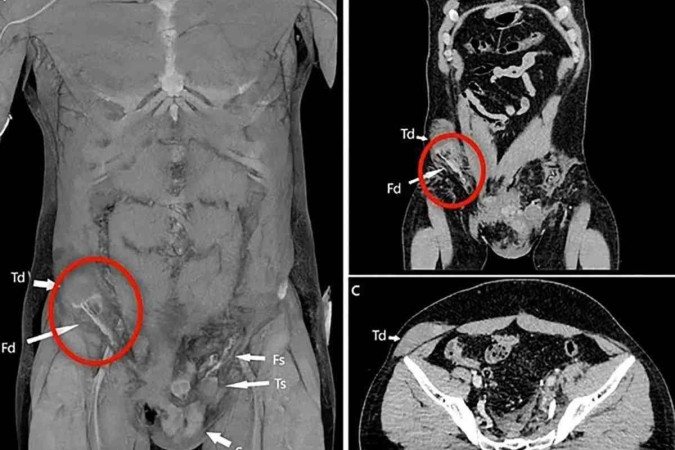

Por meio de tomografia, os médicos conseguiram ver que para onde o testículo havia se deslocado e concluíram o diagnóstico. Os especialistas precisaram operar o homem para colocar o órgão de volta no lugar.